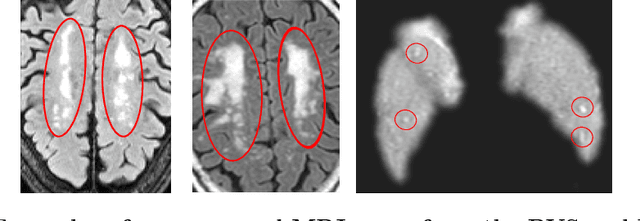

Abstract:Imaging markers of cerebral small vessel disease provide valuable information on brain health, but their manual assessment is time-consuming and hampered by substantial intra- and interrater variability. Automated rating may benefit biomedical research, as well as clinical assessment, but diagnostic reliability of existing algorithms is unknown. Here, we present the results of the \textit{VAscular Lesions DetectiOn and Segmentation} (\textit{Where is VALDO?}) challenge that was run as a satellite event at the international conference on Medical Image Computing and Computer Aided Intervention (MICCAI) 2021. This challenge aimed to promote the development of methods for automated detection and segmentation of small and sparse imaging markers of cerebral small vessel disease, namely enlarged perivascular spaces (EPVS) (Task 1), cerebral microbleeds (Task 2) and lacunes of presumed vascular origin (Task 3) while leveraging weak and noisy labels. Overall, 12 teams participated in the challenge proposing solutions for one or more tasks (4 for Task 1 - EPVS, 9 for Task 2 - Microbleeds and 6 for Task 3 - Lacunes). Multi-cohort data was used in both training and evaluation. Results showed a large variability in performance both across teams and across tasks, with promising results notably for Task 1 - EPVS and Task 2 - Microbleeds and not practically useful results yet for Task 3 - Lacunes. It also highlighted the performance inconsistency across cases that may deter use at an individual level, while still proving useful at a population level.